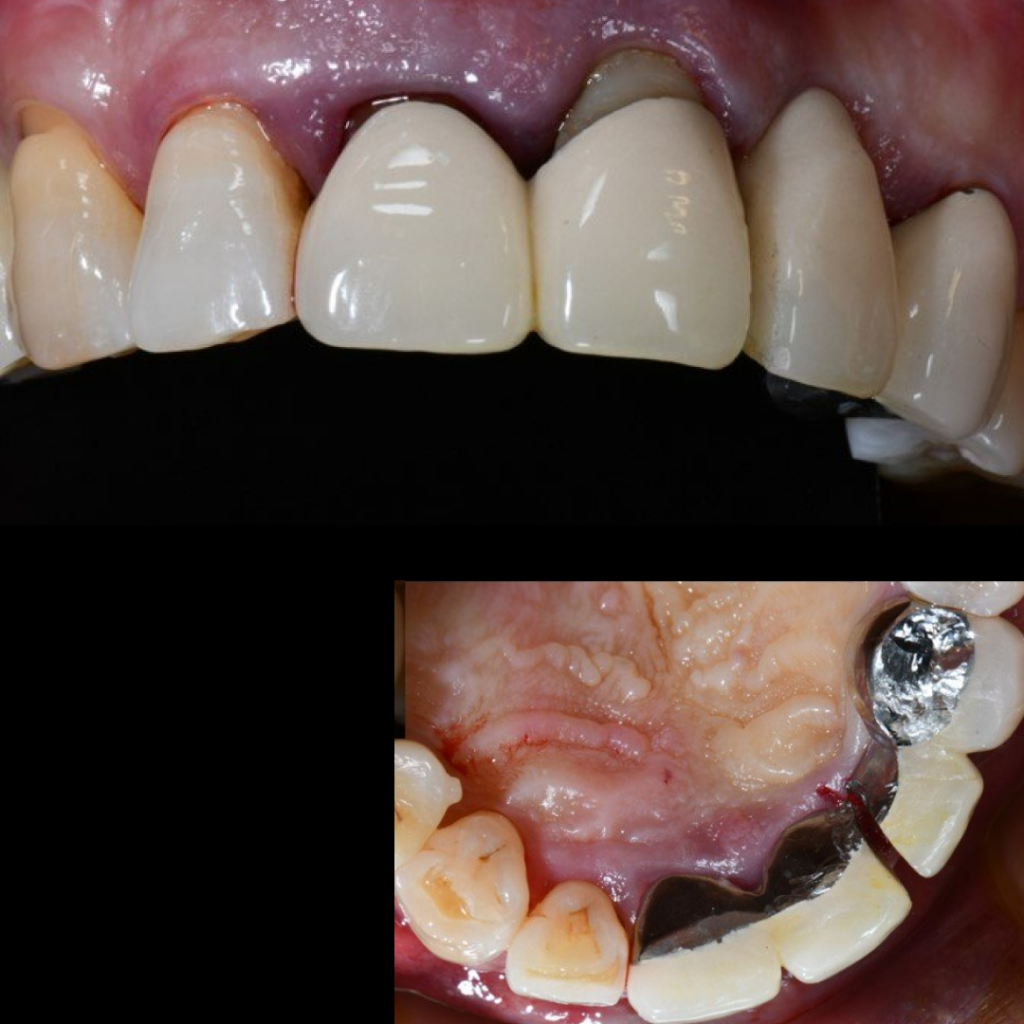

- Установка абатментов для временного протеза

- Покрытие зоны аугментации коллагеновой мембраной

- Фиксация временного мостовидного протеза

Благодаря уникальному дизайну имплантатов AnyRidge становится возможным получить блестящую первичную стабильность даже при наличии объемных костных дефектов, что позволяет в большинстве случае дать немедленную нагрузку на имплантаты и зафиксировать временный мостовидный протез

в эстетически значимой зоне в день операции.